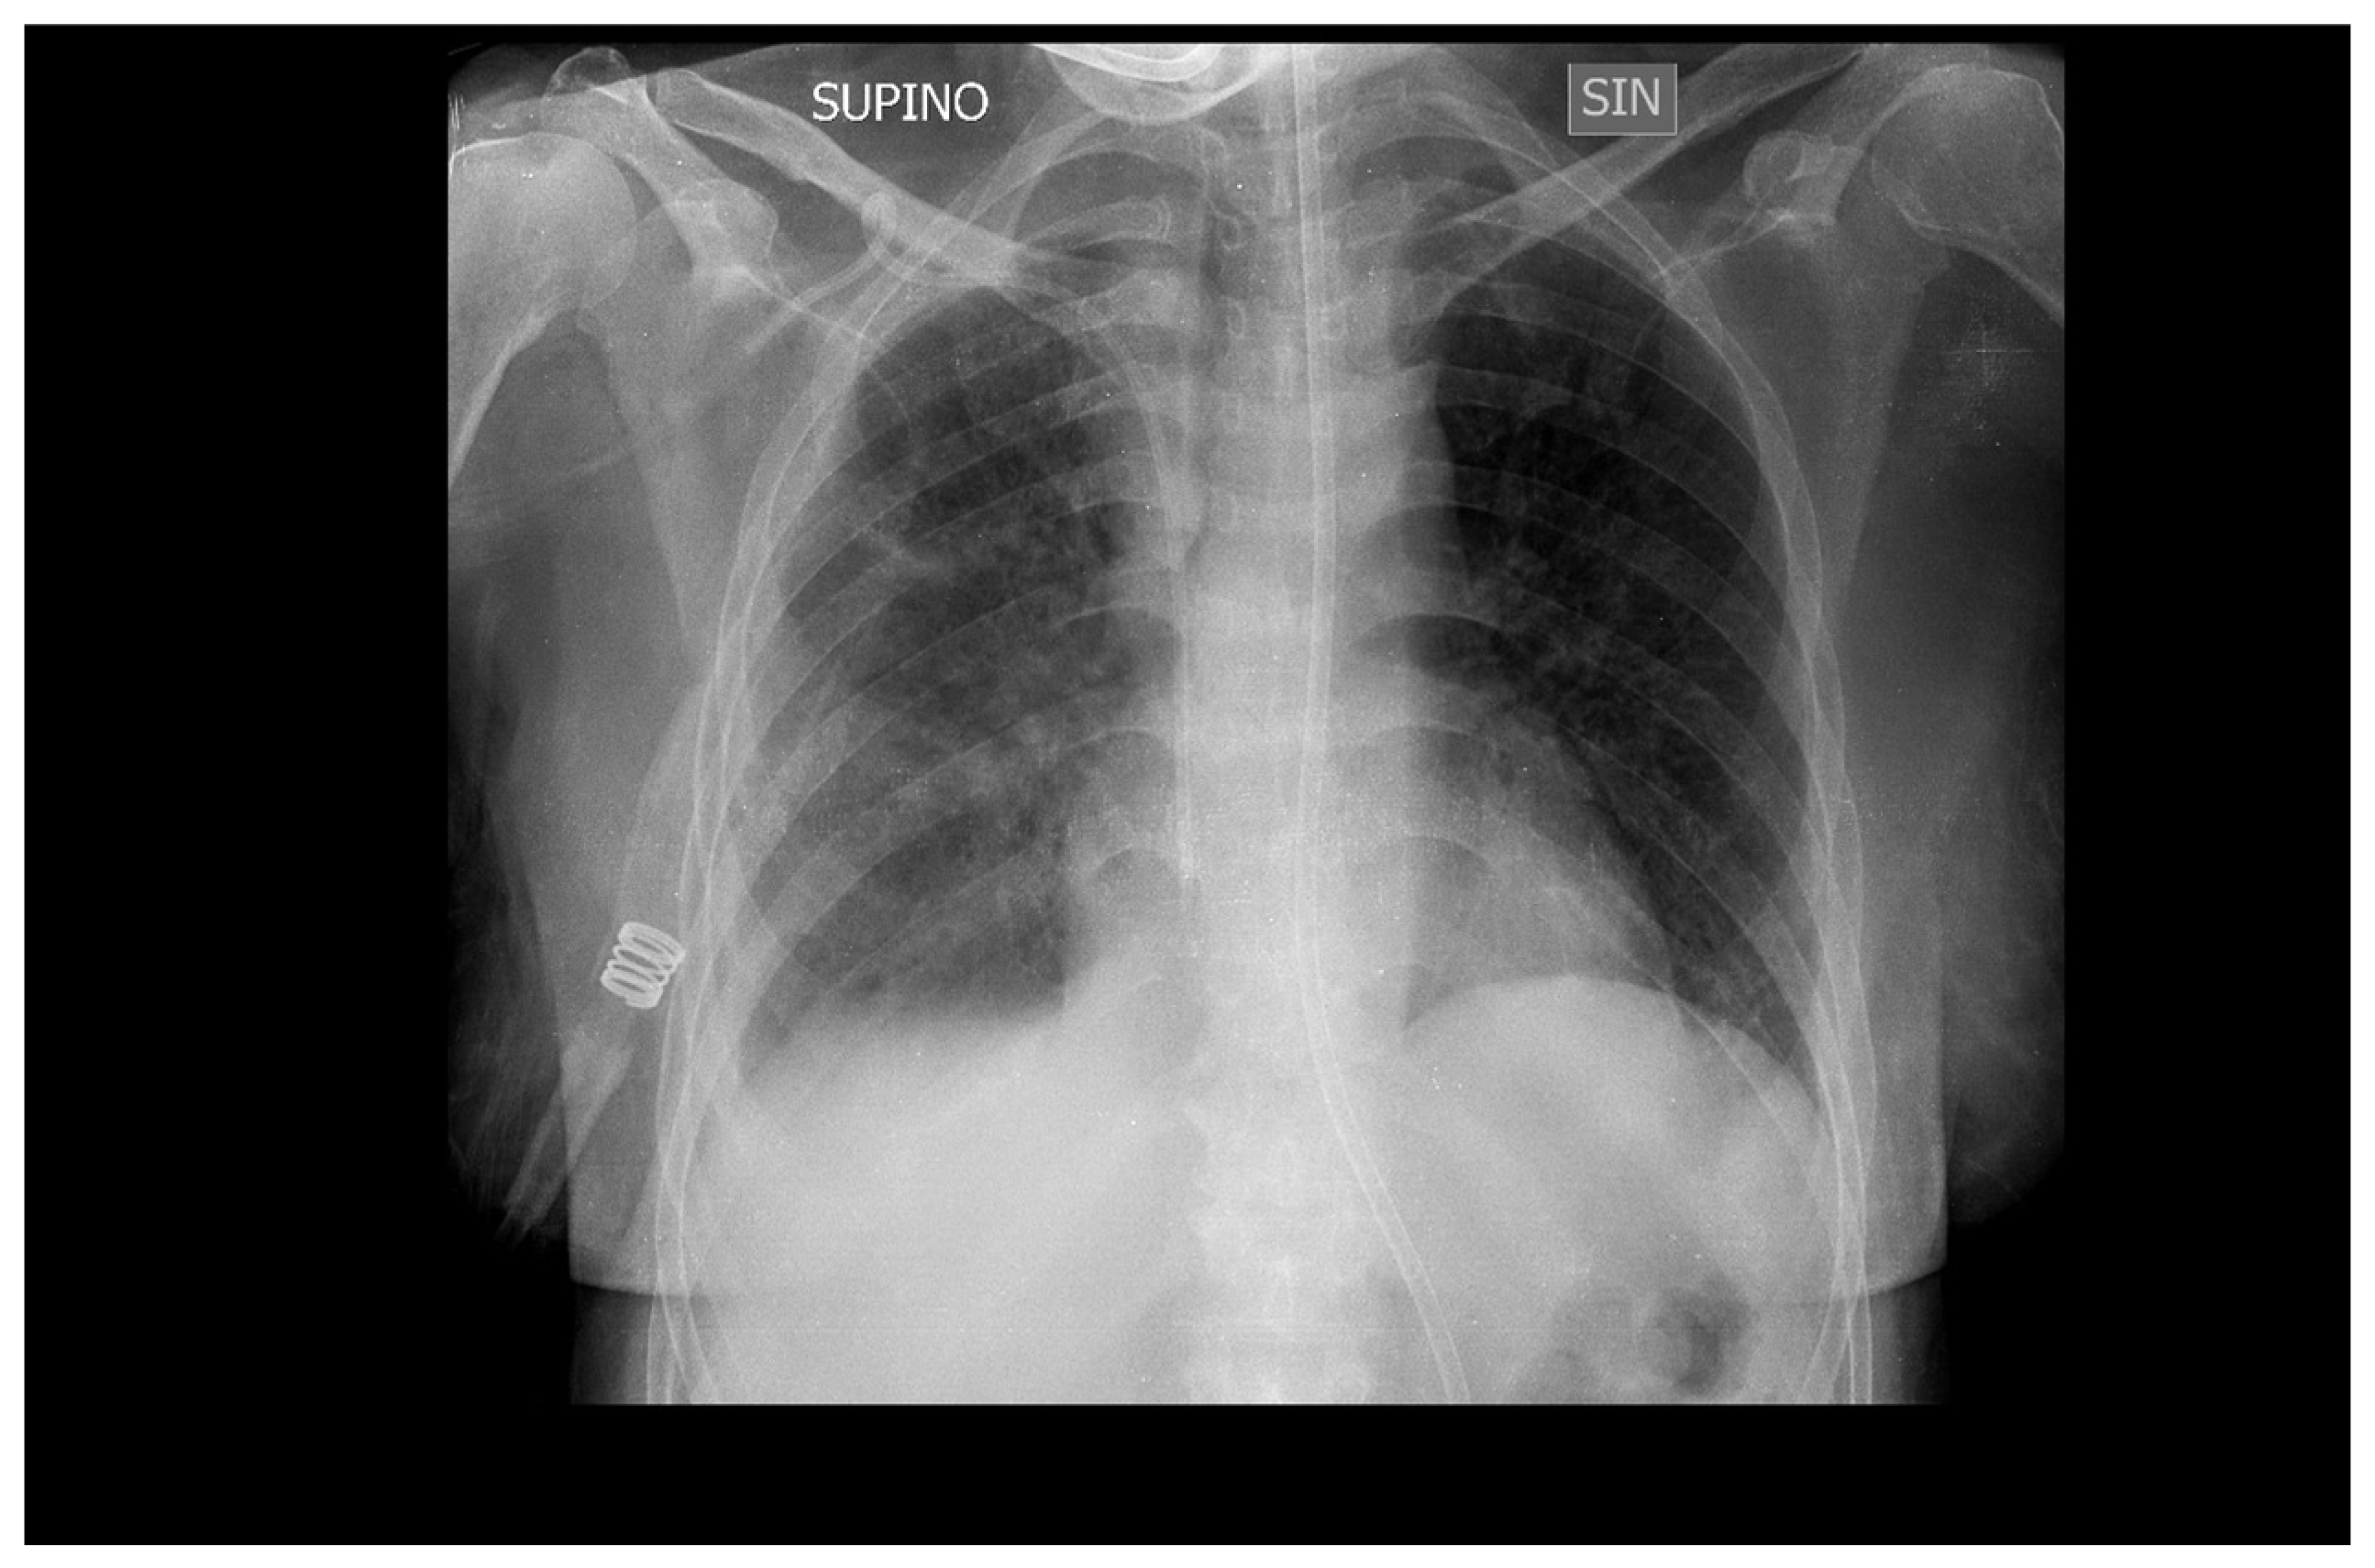

Mechanical ventilation was stopped after 10 days (Figure 4) and the patient was transferred to the medical department where she continued therapy with Ganciclovir for another two weeks before being discharged to her home.

Figure 4. Chest x-ray of a patient extubated after 10 days of Ganciclovir therapy.